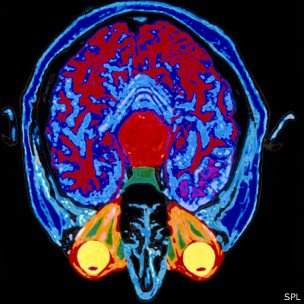

Usando una técnica llamada imagen por resonancia magnética funcional, los neurocientíficos pueden poner a alguien en un escáner y ver qué partes del cerebro se activan cuando hacen o piensan en algo.

Incluso al dormir, el cerebro se mantiene activo, como muestra esta imagen de la actividad al soñar.

Incluso al dormir, el cerebro se mantiene activo, como muestra esta imagen de la actividad al soñar.